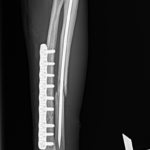

猫さんがご自宅の2Fから落下したとのことで、かかりつけ医を受診されました。右の橈骨尺骨骨折が確認されました。2.4 Titnium Locking Plate(Distal 3holeストレート)、尺骨1.6mm Titanium Wireで固定術を行いました。猫は高いところで遊ぶのが好きな動物なので、遊び場に危険な場所がないか?生活環境を見直す必要があります。